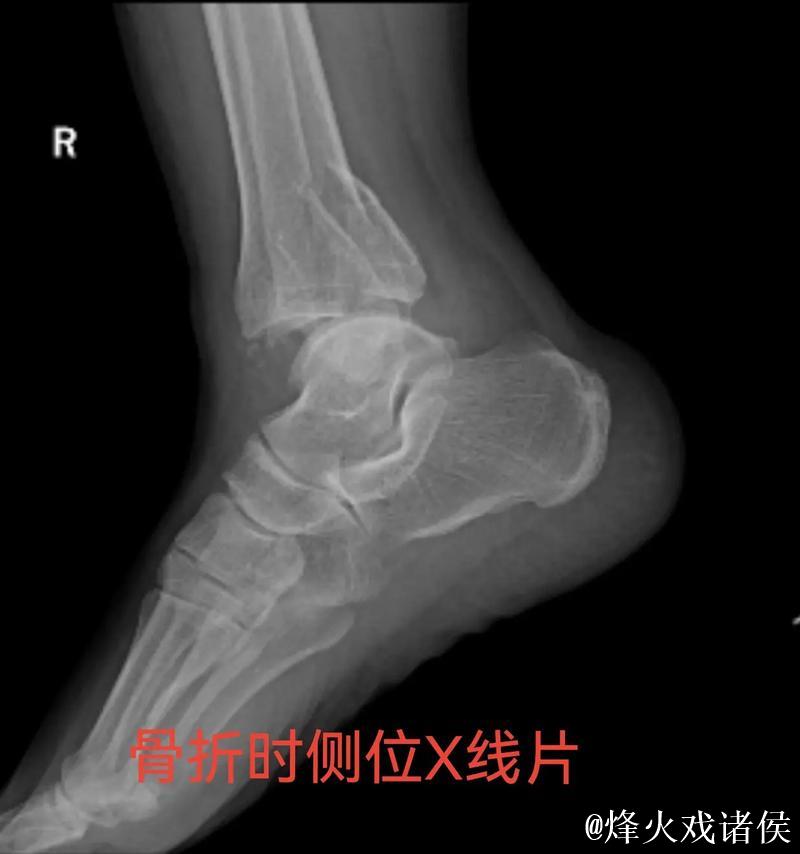

很多人在看到“右踝三角韧带断裂 右侧腓骨骨折”这样的医学表述时,只会感觉到“很严重”三个字,却未必真正理解其中的含义。踝关节三角韧带位于脚踝内侧,是一个由多条韧带组成的“组合体”,主要负责保持踝关节的内外稳定,防止小腿和足部出现异常翻转。当运动员在高速突破、急停、变向或落地时,如果脚踝遭遇过度外翻或扭转,三角韧带就可能被强行拉伸甚至撕裂。完全断裂不仅会造成剧烈疼痛,还会直接破坏踝关节的稳定性,使人几乎无法正常负重行走。与之同时出现的右侧腓骨骨折,大多与剧烈外力撞击或扭转应力有关。腓骨虽然不像胫骨那样承担大部分体重,但在踝关节的力学链条中起到重要支撑和协同作用。当韧带与骨骼在一次意外中同时受损,就意味着踝关节遭遇了极端应力,恢复与康复的难度成倍增加。

对于三角韧带断裂与腓骨骨折这种组合伤情,医学团队通常会综合评估踝关节稳定性、骨折位置与移位程度、软组织损伤范围,来决定是否采用手术治疗。若存在明显关节不稳或骨折移位,往往需要通过钢板、螺钉或钉棒内固定来重建骨性与韧带结构。在此之后,便是漫长而细致的康复周期。一般而言,骨折在数周内可以初步愈合,但韧带修复与功能恢复远比“骨头长好”更复杂。康复过程需要一套循序渐进的计划:早期的消肿与被动活动、中期的肌力与本体感觉训练、后期的专项运动模拟。每一个阶段若处理不当,都可能导致关节僵硬、力量不足或反复崴脚等后遗症。对职业运动员来说,问题不仅是“能不能走路”,而是“能不能继续高强度比赛、能不能保持原有水平”。任何轻微的落差,都可能在激烈竞争的职业舞台上被放大。